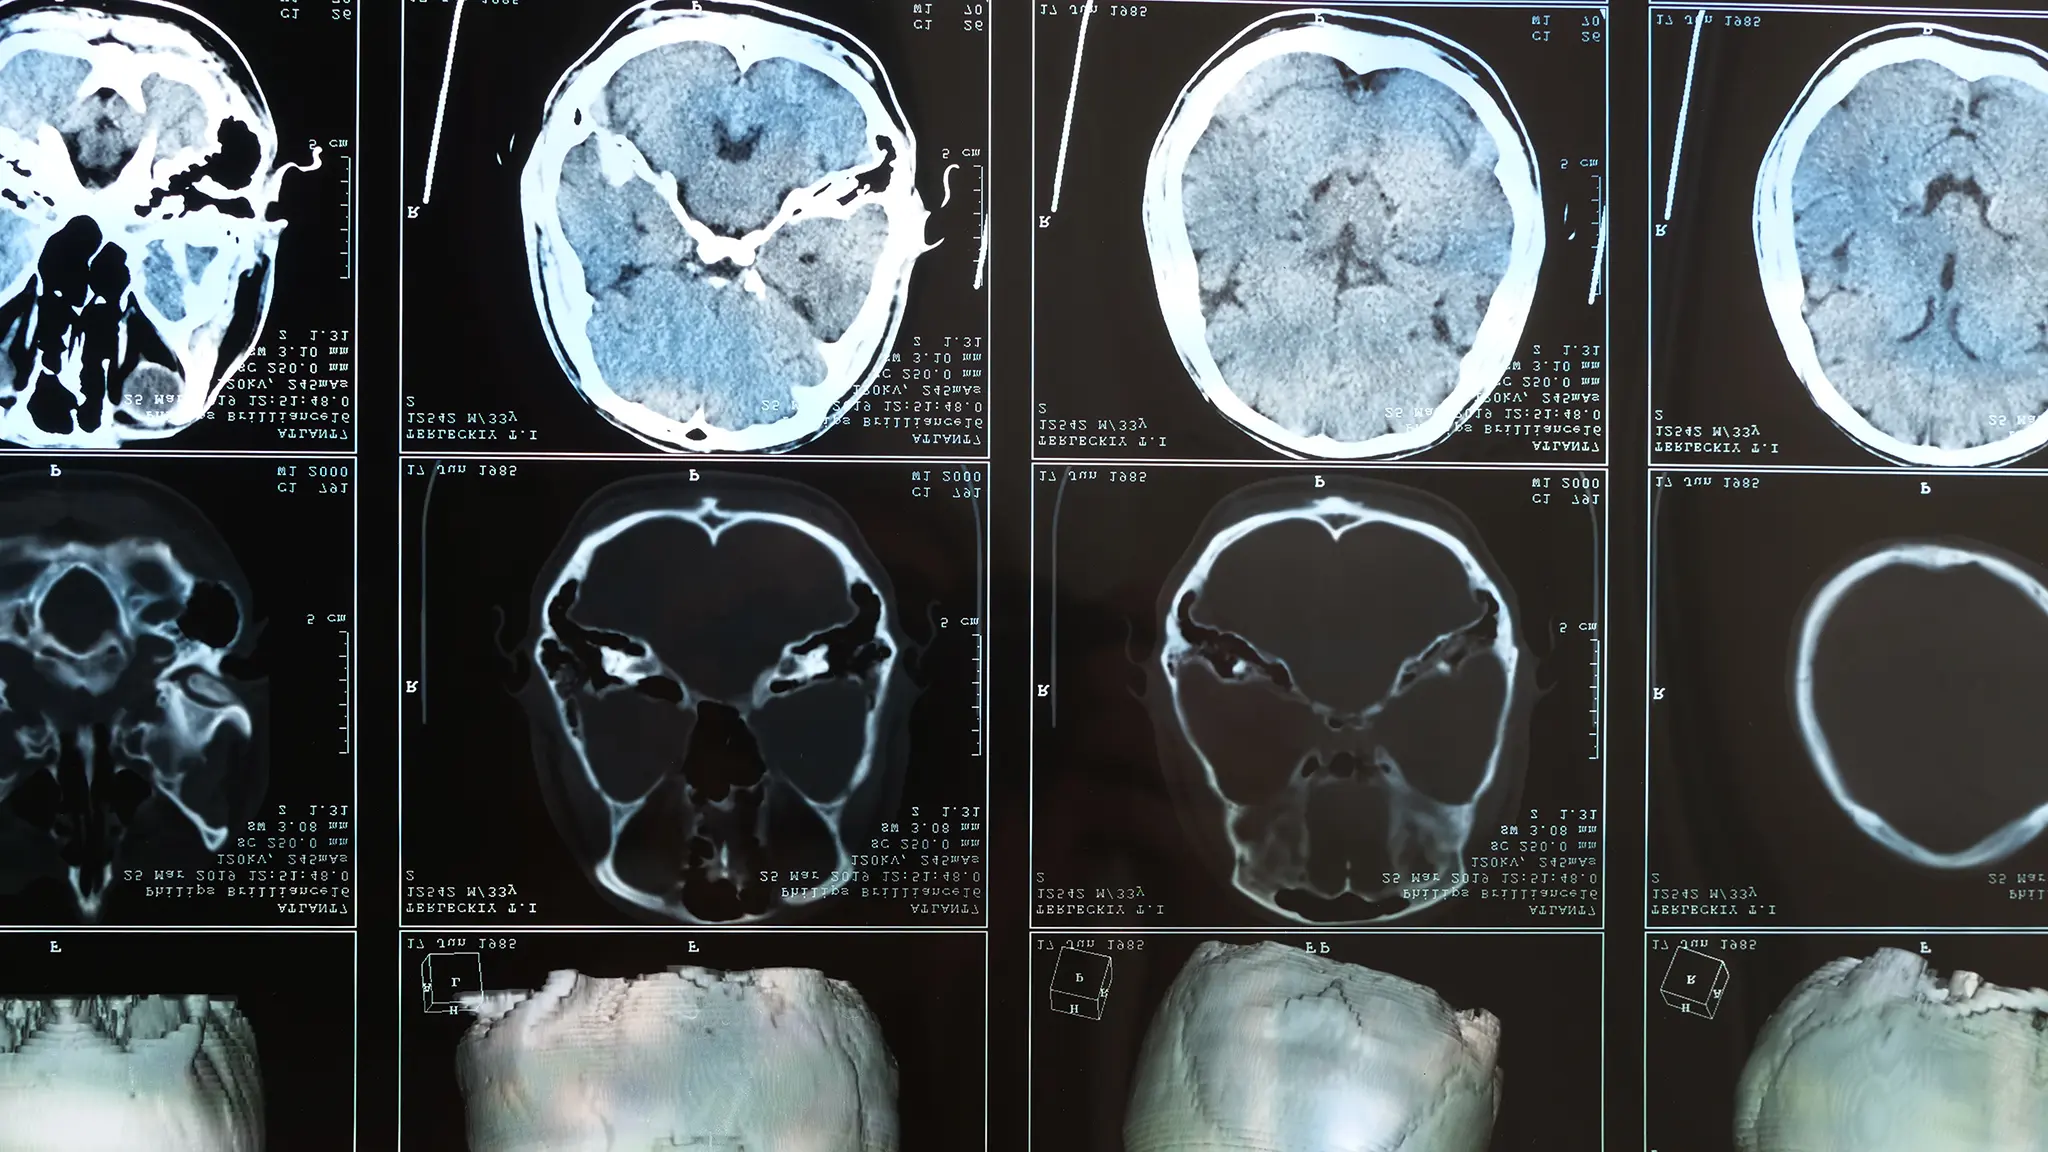

A TBI occurs when a sudden impact or jolt disrupts normal brain function. Even what seems like a “mild” concussion can have serious long-term consequences. Because symptoms may take hours or days to appear, immediate medical evaluation is critical — and so is having a law firm that understands how to prove invisible injuries in court.

Not all TBIs show up on imaging. Many involve microscopic damage. Our experts use neurocognitive testing and other tools to prove your injury’s impact.